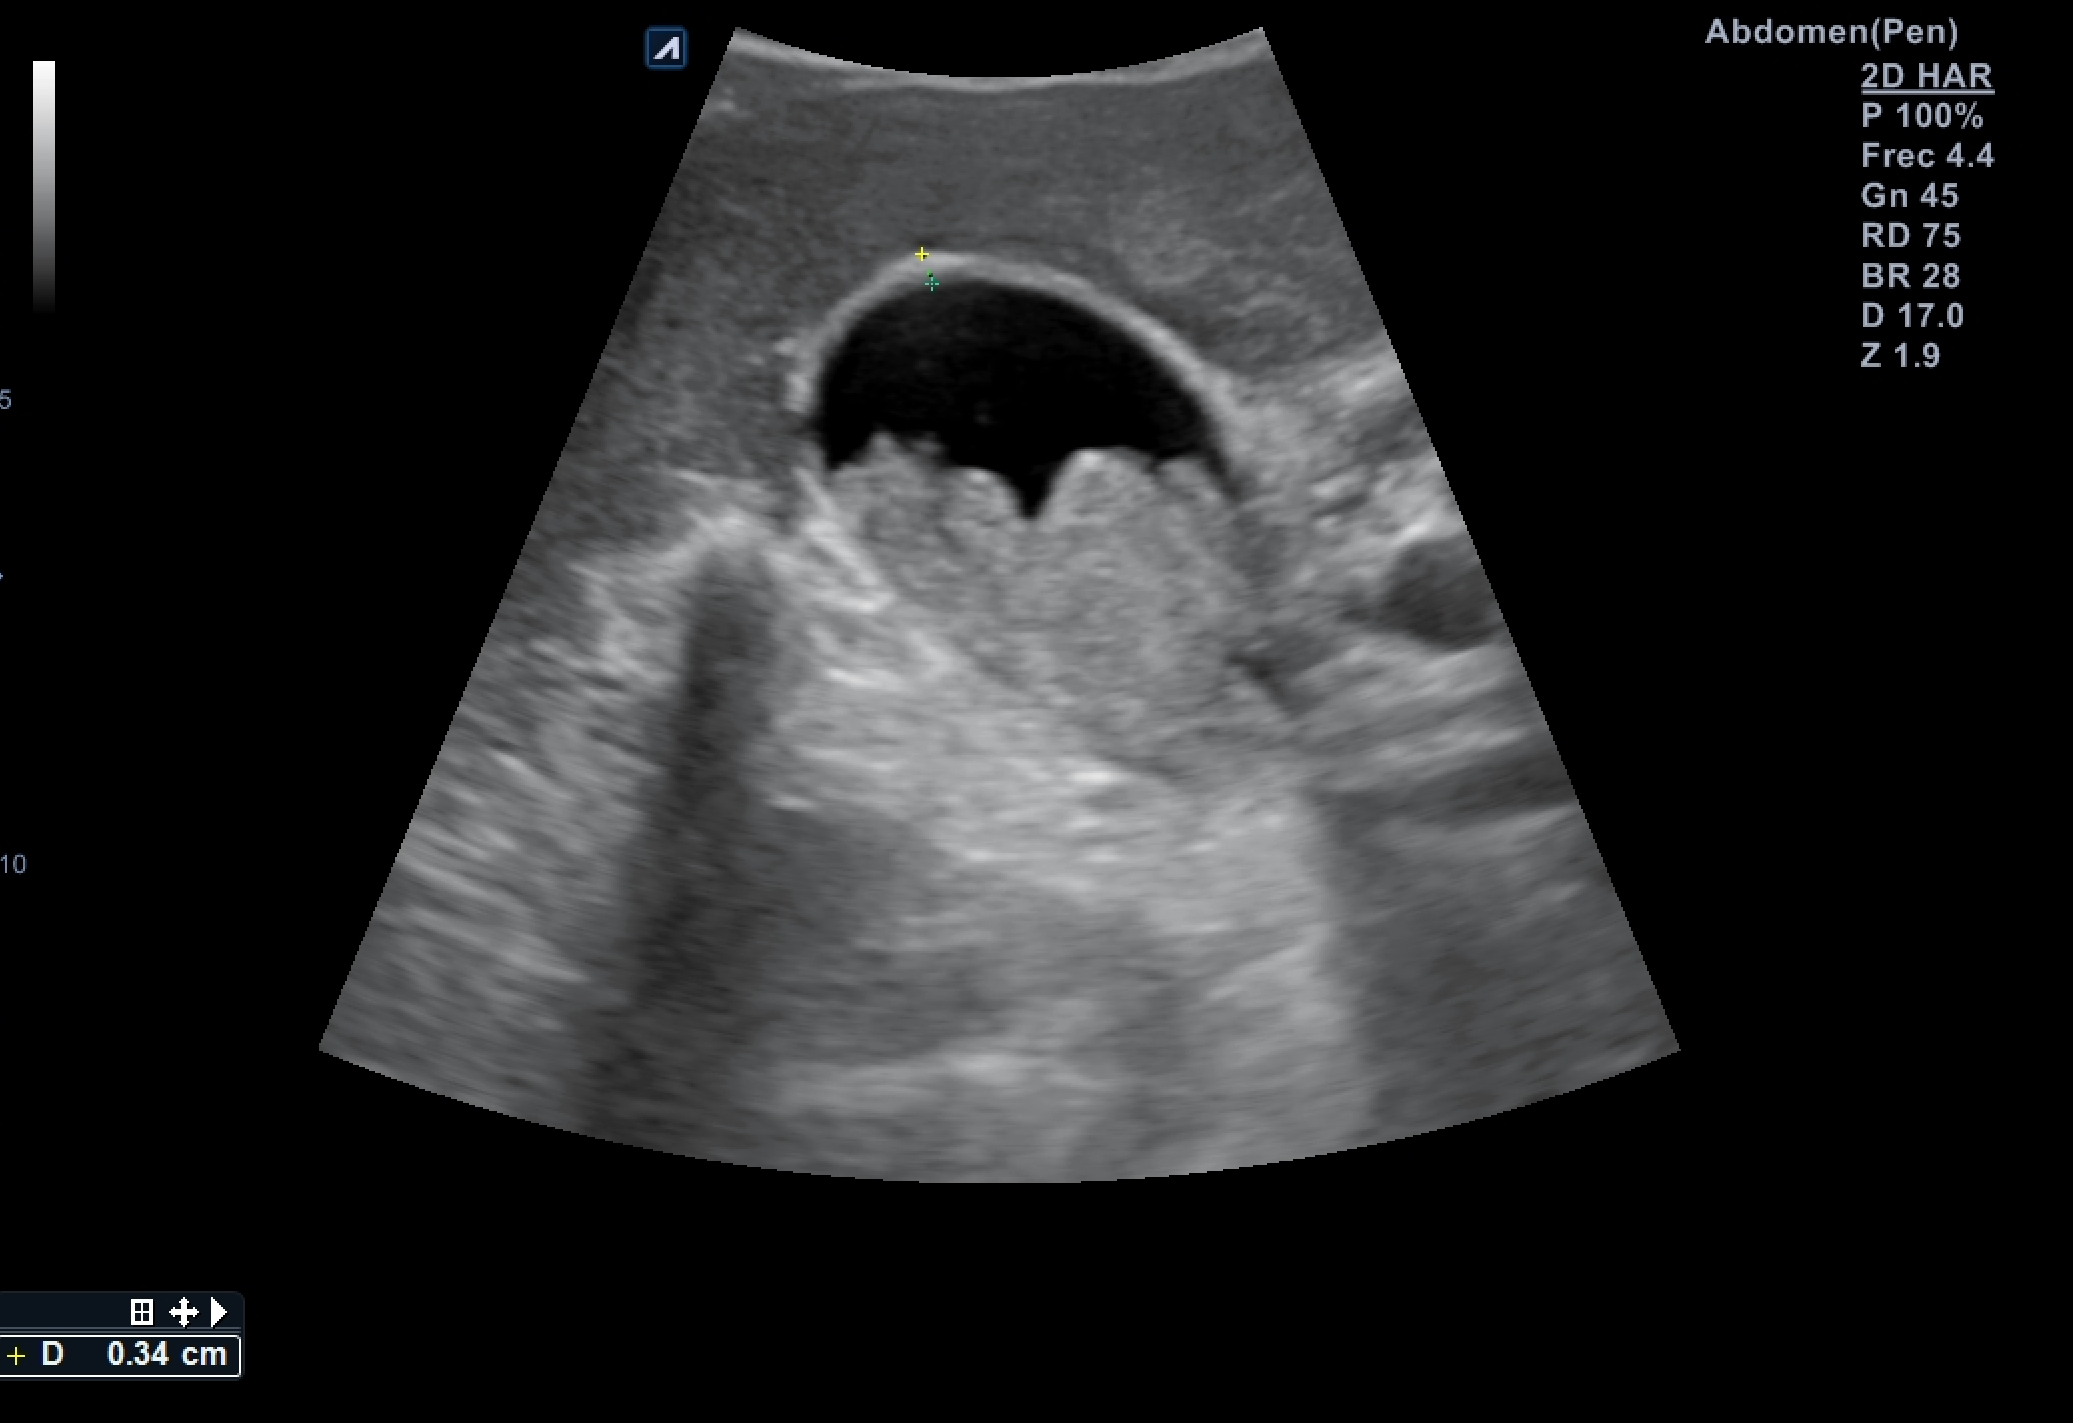

Ecografía abdominal dónde destaca vesícula biliar de pared fina (hasta 3,4 milímetros en su punto de mayor grosor) sin colecciones perivesiculares, que alberga en su interior imagen polilobulada sólida de efecto masa dependiente de su pared posterolateral e inferior que ocupa más de la mitad de la luz, sin captación de flujo Doppler, sugerente de polipoidea o tumoral, de unos 6 x 5 x 3 centímetros de dimensiones mayores.